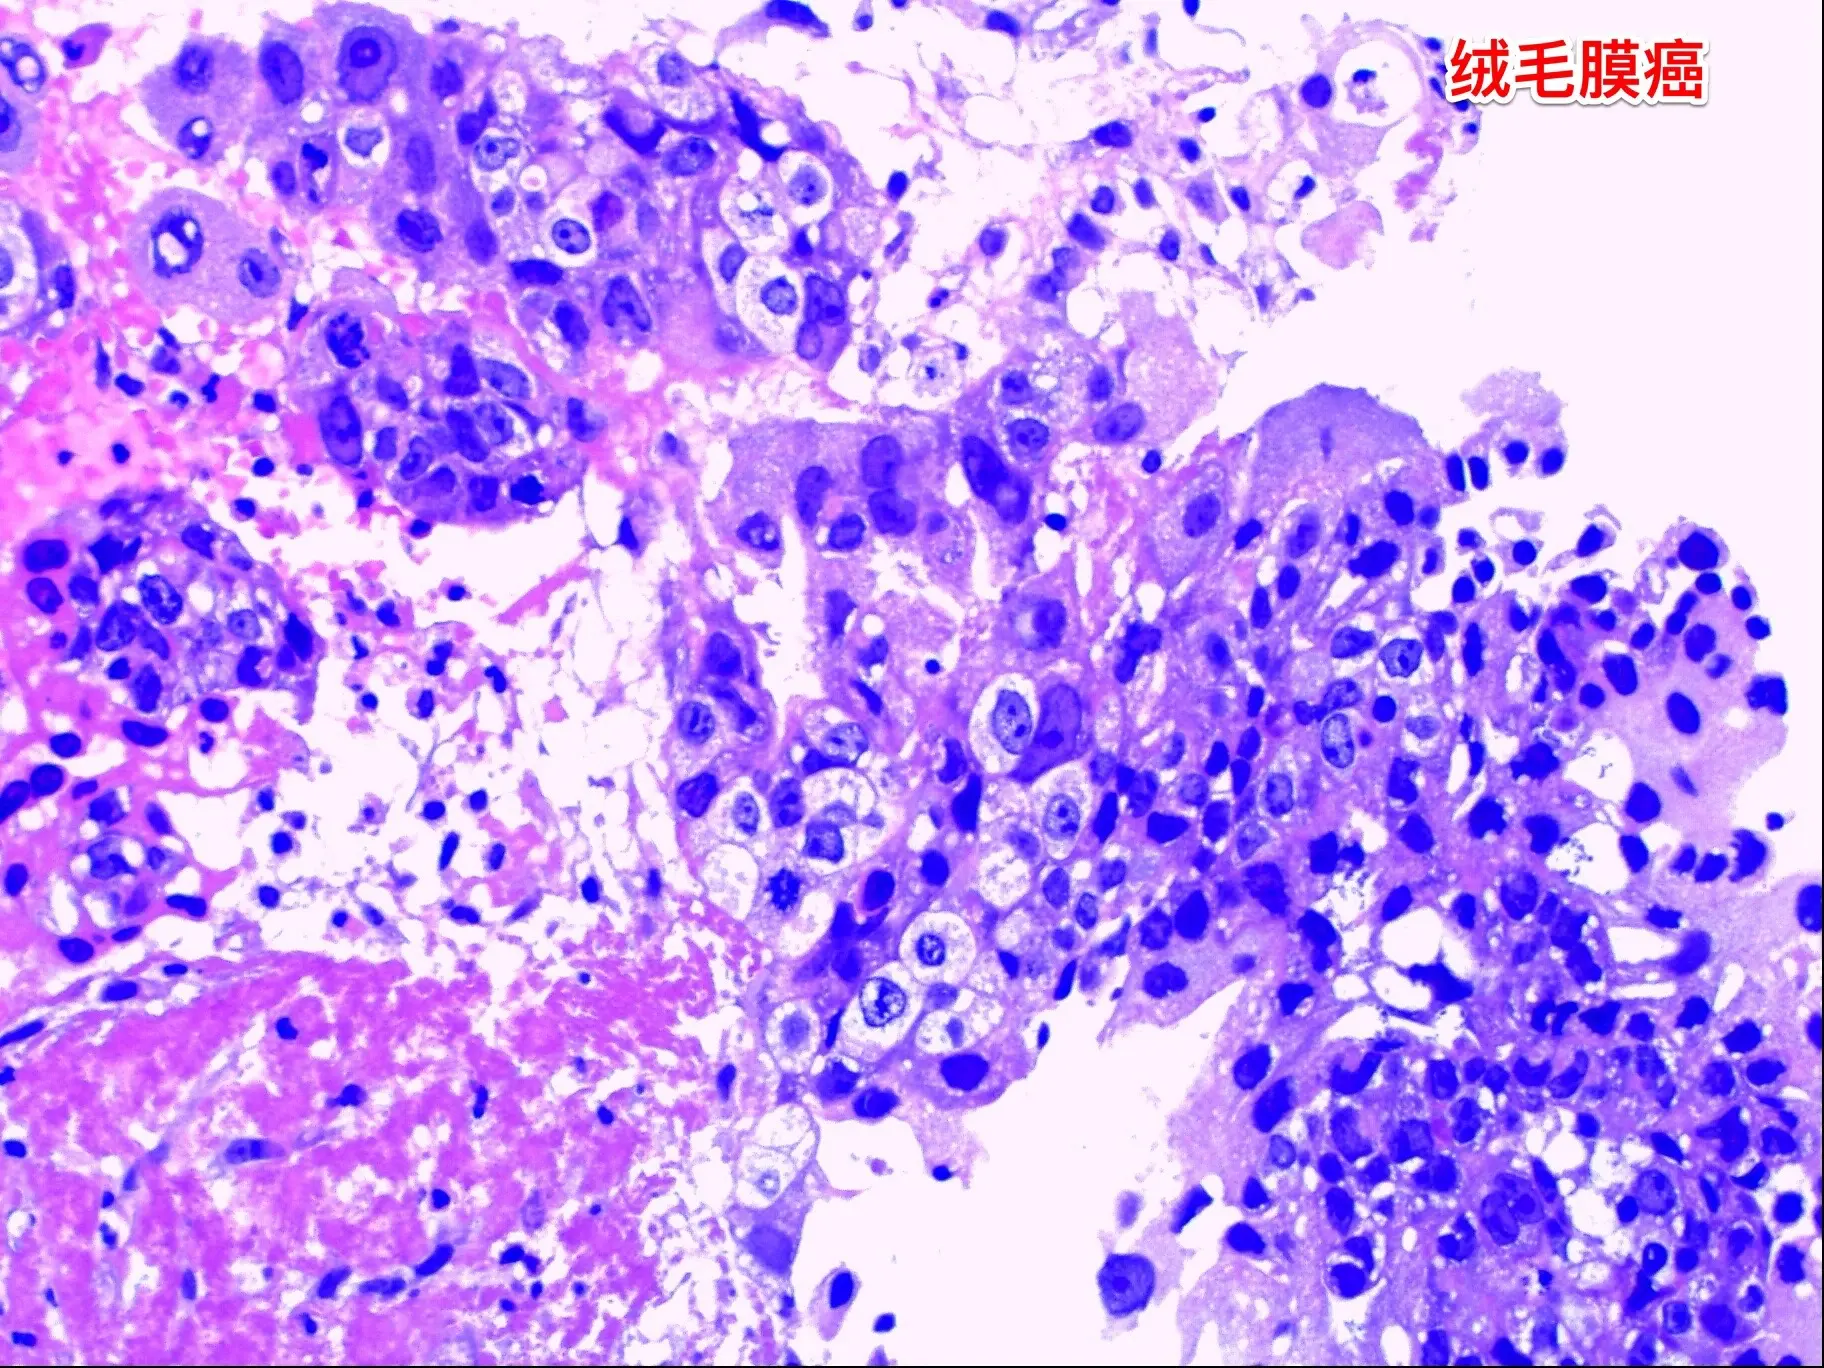

松果体区的绒毛膜癌(绒癌)很罕见。通常情况下,绝大多数的绒癌与女性怀孕过程的滋养细胞有关系,可以造成子宫内出血。 但是,脑部有一种恶性肿瘤称为绒癌,是生殖细胞肿瘤中的一种,很罕见,一般见于鞍区和松果体区。 这个11岁济宁市的男孩子于2024年10月底18日突发头痛、恶心、呕吐,在当地医院行头部CT检查发现了脑部有出血,出血的位置位于松果体区及第三脑室里,和普通的脑出血位置不一样。经过急诊手术(脑室外引流术)后保住了生命。磁共振检查显示松果体区有个肿瘤,考虑是肿瘤卒中出血了。转到我院化验HCG,达到正常值的600多倍。 2024年10月27日在我科作了手术,将肿瘤切除了,手术后小男孩身体恢复顺利,HCG逐步下降到正常范围。病理报告是纯绒癌! 这个脑部的绒癌是生殖细胞肿瘤中的一种,恶性度高,手术后需要作化疗+放疗。